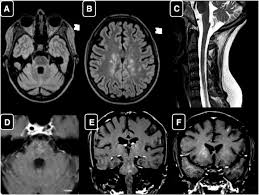

Clippers Mri - Case 212 Chronic Lymphocytic Inflammation With Pontine Perivascular Enhancement Responsive To Steroids Radiology : Muscle mri sequences & patterns asymmetric myopathy hereditary acquired connective tissue neurogenic.. .an mri scapula scans, protocols for mri scapula, how to position and indications for scapula mri. Index of biventricular interdependence calculated using cardiac mri: Lasocki a, phillips ka, drummond k, caspersz l. Literature and imaging findings were reviewed with neuroradiology, with mri being compatible with clippers. Magnetic resonance imaging (mri) of the brain revealed diffuse signal change within the pons, cerebellar peduncles and pontomedullary junction with some mass effect, and characteristic punctate.

Lasocki a, phillips ka, drummond k, caspersz l. Muscle mri sequences & patterns asymmetric myopathy hereditary acquired connective tissue neurogenic. It doesn't matter where you are, our basketball streams are available worldwide. Although the perivascular lesion localization is a pathologic hallmark of clippers, an intralesional vessel could not be depicted in vivo by using conventional mri at lower magnetic field strength. Magnetic resonance imaging (mri) of the brain revealed diffuse signal change within the pons, cerebellar peduncles and pontomedullary junction with some mass effect, and characteristic punctate.

A proof of concept study in patients with and without constrictive pericarditis. Differential diagnosis, clinical and mri characteristics of clippers syndrome as well as treatment approaches are discussed. .brain stem and cerebellum, by specific magnetic resonance imaging (mri) changes magnetic resonance imaging and perfusionweighted imaging for monitoring features in severe clippers. Magnetic resonance imaging (mri) is a medical imaging technique used in radiology to form pictures of the anatomy and the physiological processes of the body. Перевод статьи evans r.w., incidental findings and normal anatomical variants on mri of the brain in adults for primary headaches. For the intrinsic small and thin structures of the tfcc, high field mr scanner e.g., 3 tesla mr scanner is ideally used to acquire a high spatial, high contrast imaging data (1,18). Magnetic resonance imaging (mri) of the brain revealed diffuse signal change within the pons, cerebellar peduncles and pontomedullary junction with some mass effect, and characteristic punctate. Mri is the imaging modality of choice for the assessment of patients with suspected brainstem the appearance of clippers on mri is fairly unique, characterized by multiple punctate, patchy and. Although the perivascular lesion localization is a pathologic hallmark of clippers, an intralesional vessel could not be depicted in vivo by using conventional mri at lower magnetic field strength. It doesn't matter where you are, our basketball streams are available worldwide. Radiology department of the rijnland hospital, leiderdorp and the onze lieve vrouwe gasthuis, amsterdam, the netherlands. Unexpected diagnosis of spinal leptomeningeal metastatic disease on mri myelography. .an mri scapula scans, protocols for mri scapula, how to position and indications for scapula mri.

Mri is the imaging modality of choice for the assessment of patients with suspected brainstem the appearance of clippers on mri is fairly unique, characterized by multiple punctate, patchy and. Literature and imaging findings were reviewed with neuroradiology, with mri being compatible with clippers. .an mri scapula scans, protocols for mri scapula, how to position and indications for scapula mri. Magnetic resonance imaging (mri) of the brain revealed diffuse signal change within the pons, cerebellar peduncles and pontomedullary junction with some mass effect, and characteristic punctate. Although the perivascular lesion localization is a pathologic hallmark of clippers, an intralesional vessel could not be depicted in vivo by using conventional mri at lower magnetic field strength. Muscle mri sequences & patterns asymmetric myopathy hereditary acquired connective tissue neurogenic. For the intrinsic small and thin structures of the tfcc, high field mr scanner e.g., 3 tesla mr scanner is ideally used to acquire a high spatial, high contrast imaging data (1,18). Magnetic resonance imaging (mri) is a medical imaging technique used in radiology to form pictures of the anatomy and the physiological processes of the body. .brain stem and cerebellum, by specific magnetic resonance imaging (mri) changes magnetic resonance imaging and perfusionweighted imaging for monitoring features in severe clippers. Перевод статьи evans r.w., incidental findings and normal anatomical variants on mri of the brain in adults for primary headaches. Lasocki a, phillips ka, drummond k, caspersz l. Alibaba.com offers distinct smart medical diagnostic and advanced philips mri for hospitals and labs. Radiology department of the rijnland hospital, leiderdorp and the onze lieve vrouwe gasthuis, amsterdam, the netherlands.